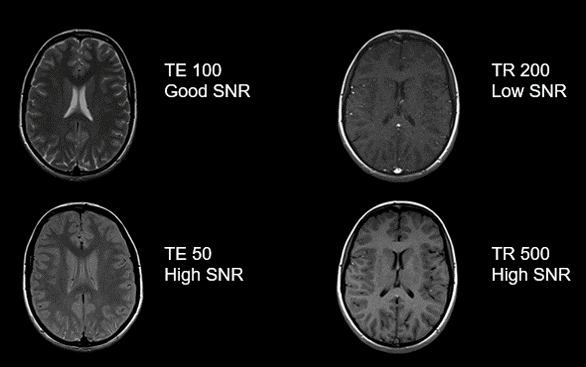

TE and TR:

Recall TE means “Time to Echo”. Also, recall that the longer we wait to collect the echo, the weaker the signal because as time passes T1 and T2 relaxation come to an end. For this reason, a short TE will give a stronger signal than a longer TE. Compare the images to the left. Note that both images have decent signal, though the image with a TE of 50 has higher SNR. However, notice the difference in T2 contrast – because TE also controls T2 contrast it is not always the parameter of choice to change to control SNR and can only be changed within a range that will not change the desired contrast of the image.

While TR does not directly affect the amount of noise in an image, it needs to be discussed here because longitudinal magnetization will allow SNR to be at its greatest appearance. A longer TR, or time before repetition, allows for more recovery thus allowing for greater longitudinal magnetization, thus optimizing Signal to Noise ratio. However, notice the difference in T1 contrast – because the TR controls T1 contrast it is not always the parameter of choice to control SNR, and only can be changed within a range that will not alter the desired contrast of the image.